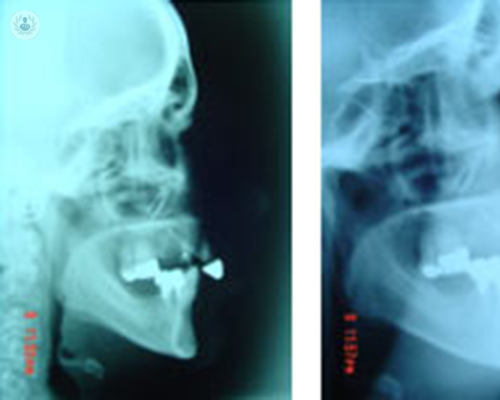

Guías y miniplacas personalizadas: un protocolo guiado para cirugía ortognática

El Dr. Joan Brunsó explica en qué medida ha ayudado la introducción de la tecnología en el tratamiento de problemas orales y maxilofaciales, como la cirugía ortognática. Conoce en qué consisten las guías y las miniplacas en cirugía ortognática, los métodos y los materiales utilizados...